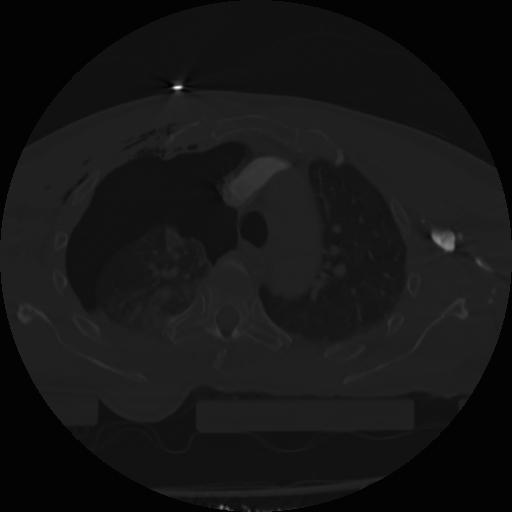

22 ANGIO,CE,Vol,0.5,ANGIO,,